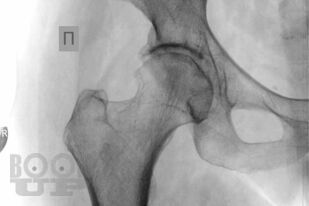

В основу книги положен многолетний опыт ультразвуковых исследований тазобедренного сустава в многопрофильной клинике с развитыми ревматологической и ортопедической службами. Проанализирован опыт отечественных и зарубежных авторов, суммированы результаты многочисленных оригинальных собственных исследований. Подробно освещены вопросы топографической и ультразвуковой анатомии тазобедренного сустава, технические особенности проведения исследования в том числе с использованием контрастных препаратов, проведения внутрисуставных инъекций под контролем ультразвукового исследования. Подробно описаны особенности ультразвуковой визуализации неизмененного тазобедренного сустава, широкого спектра патологических состояний и заболеваний дегенеративно-дистрофического, травматического, воспалительного генеза при использовании новейших и инновационных технологий эхографии. Дано подробное описание ультразвуковой картины при различных состояниях сустава: от асептического некроза головки бедренной кости, артрита, трохантерита, бурситов до бедренно-ацетабулярного импинджмента, ARS- и хамстринг-синдромов. В монографии представлены рациональные варианты и алгоритм диагностического поиска при патологии тазобедренного сустава с применением методов лучевой визуализации, определено оптимальное место ультразвукового исследования, даны подробные варианты описательной и заключительной частей ультразвуковых протоколов.